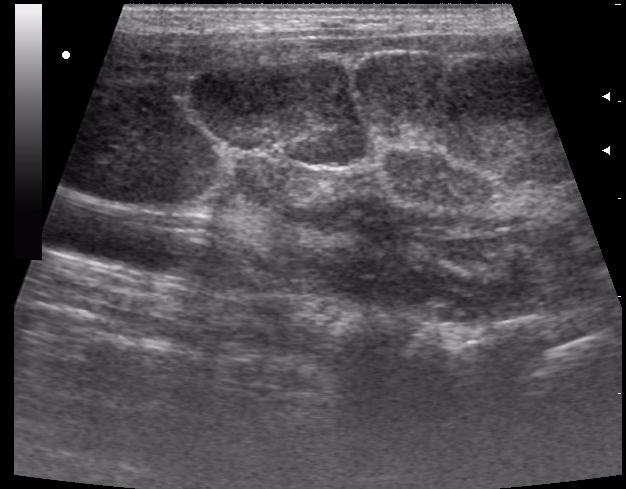

Cвинка

Re: свинка

Да уж,явное увеличение околоушных желез.Да и реакция л.узлов значительная.Интресно понаблюдать в динамике.Слишком большие подчелюстные узлы.Спасибо за случай.